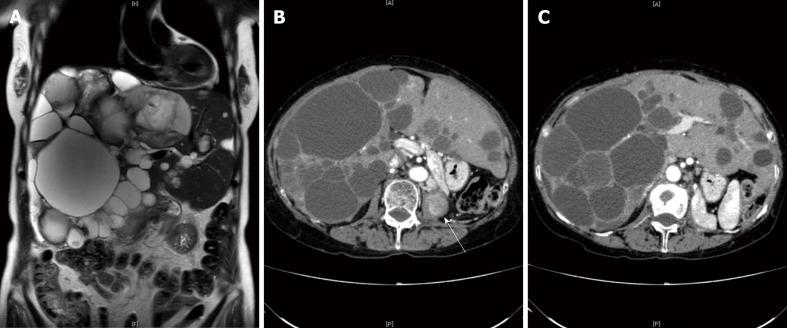

Polycystic liver disease (PCLD) with a large cystic volume deteriorates the quality of life of patients through substantial effects on the adjacent organs, recurrent cyst infections, cyst rupture, and hemorrhage. Surgical or radiological intervention is usually needed to alleviate these symptoms. We report a rare case of the cystic metastasis of renal cell carcinoma (RCC), which was misdiagnosed as PCLD, as a result of the clinical and radiological similarity between these disorders.

A 74-year-old female who had undergone nephrectomy for papillary-type RCC (PRCC) was suffering from abdominal pain and the recurrent intracystic hemorrhage of multiple cysts in the liver. Imaging studies and aspiration cytology of the cysts showed no evidence of malignancy. With a diagnosis of autosomal dominant polycystic liver disease, the patient received hepatectomy for the purpose of mass reduction and infectious cyst removal. Surgery was performed without complications, and the patient was discharged on postoperative day 14. Postoperatively, the pathology revealed a diagnosis of recurrent PRCC with cystic formation.